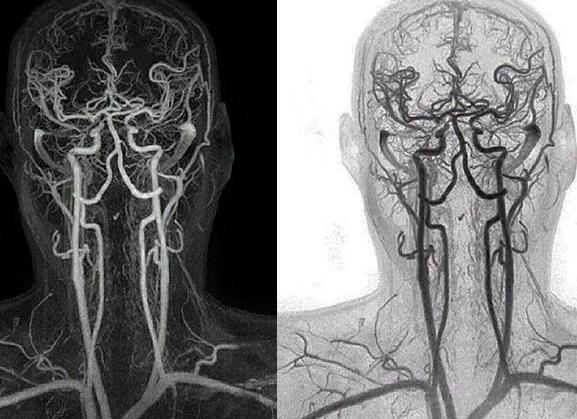

Ангиография сосудов головы и шеи

Патологические процессы могут поразить не только кости и мягкие ткани, они могут коснуться и сосудов головы и шеи. КТ головы часто не ограничивается оценкой состояния здоровья мозга и черепа, нередко этот метод дополняют сканированием сосудов головы или шеи. Сканирование сосудов мозга и шеи называется ангиографией, этот лучевой метод исследования является безопасным и высоко информативным. Ангиография сосудов головы и шеи позволяет получить подробную информацию об особенностях строения и функционирования кровеносного русла. Именно этот вид диагностики незаменим перед проведением плановых операций на сосудах. Ангиография может диагностировать:

- аномальные соустья и аневризмы;

- стеноз сосуда или его окклюзию;

- мальформации сосуда;

- изменения атеросклеротического характера.